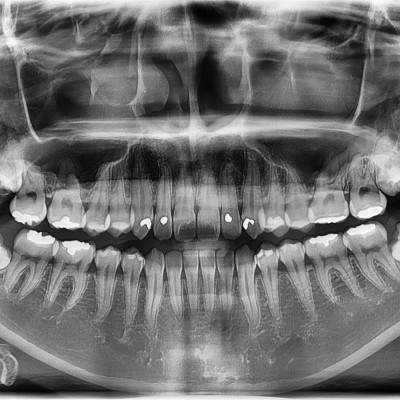

#18,28,48 사랑니 발치 #18,28,48 사랑니 발치 구강 외과 전문의가 당일 발치했습니다. ---------------------..